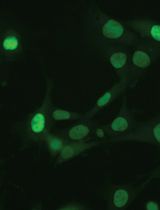

The MDA represents a combination of all the steps of retinal angiogenesis and provides a highly relevant model for the study of pro- and anti-angiogenic agents in vitro. In-depth morphological studies have shown that the angiogenic sprouting (occurring in the MDA) closely mimics retinal angiogenesis in vivo. Electron microscopy studies have demonstrated the presence of a lumen and elaborate cell–cell junctions within the endothelial cell aggregates observed in the MDA [9, 10]. As the endothelial capillary tube–like structures invade into the secondary Matrigel layer, the leading edge of the capillary sprouts is associated with long filopodia. The structure of these filopodia resembles those seen at the angiogenic front during developmental angiogenesis in the neonatal retina [9]. The retinal endothelial cells grown within the two layers of Matrigel reflect the biological characteristics of the neovascular retina, such as diffusion gradient of oxygen, nutrients, and pH. The growth of the cells inside the Matrigel duplex system allows for complex cell–cell and cell–matrix interaction. Furthermore, these retinal endothelial sprouts may be characterized and quantified by confocal microscopy [9].